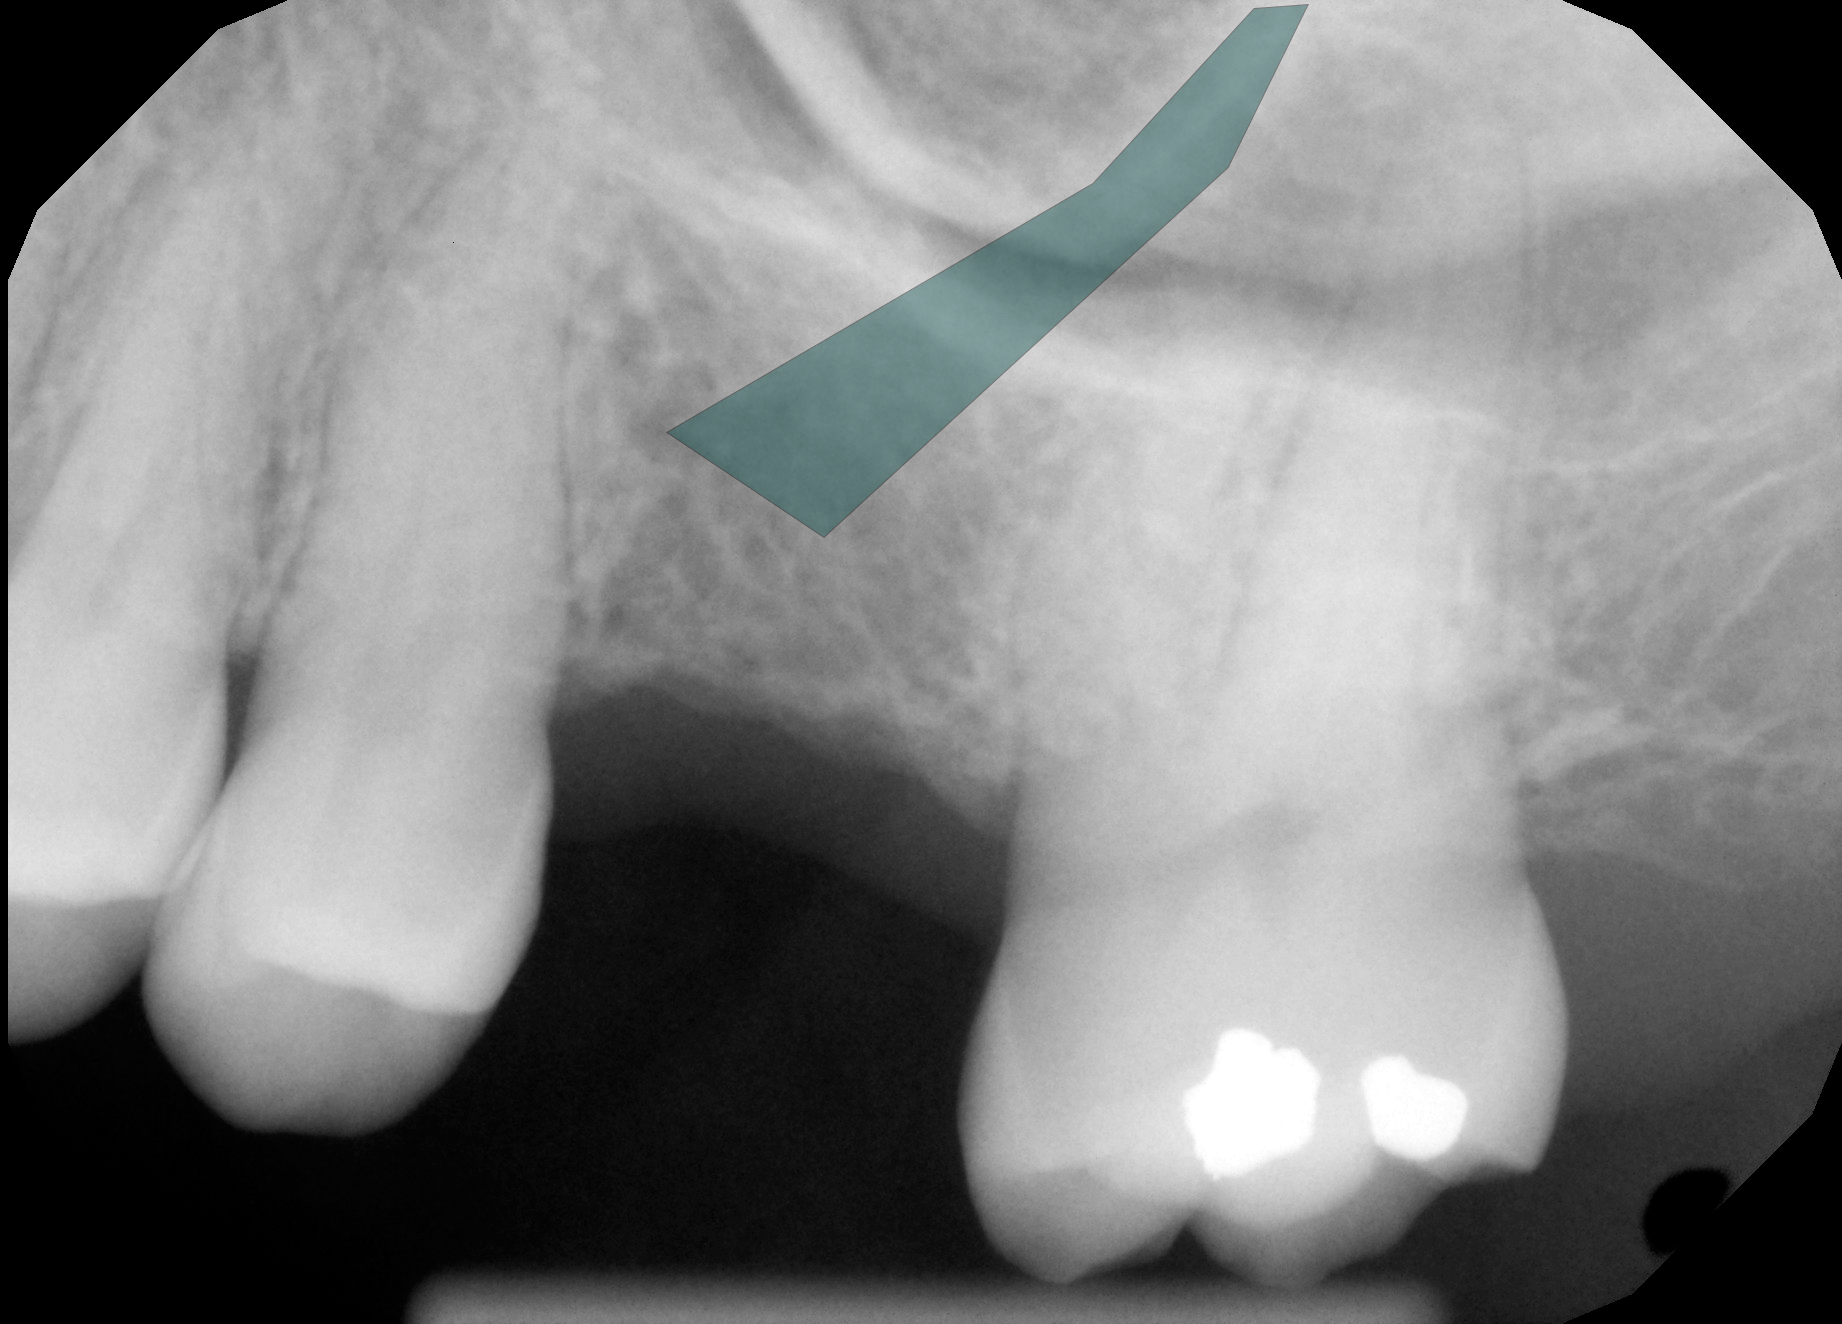

Exhibit 1: Forensic Overlay

Original Marked

Click "Show Annotation" to reveal the identified geometric object in the extraction site.